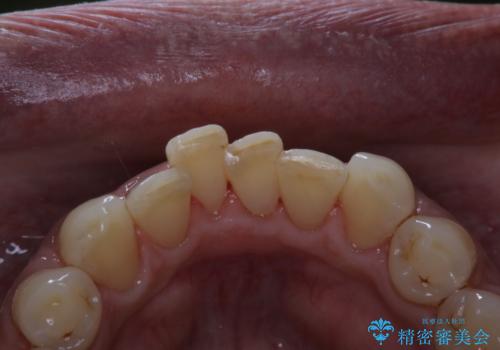

- インビザラインでの矯正治療中の方です。コーヒーをよく飲むため、着色が気になるとのことでした。PMTC60分コースを行いました。

PMTC(保険外治療)は、毎日の歯磨きで落としきれない汚れや、コーヒ、紅茶・タバコのヤニなどの着色も除去します。目には見えない歯と歯の間・歯肉の境目・インビザライン中はアタッチメント周囲などに残っているプラーク(歯垢)もしっかり取り除きます。PMTCでは専門的な機械や材料を使用して、徹底的に汚れを除去するため、虫歯・歯周病・口臭予防などにつながります。

また、仕上げのトリートメントでは歯の表面の凸凹にミネラルを補給して、ツルツルの表面に仕上げます。定期的にPMTCを行うことにより、歯質の強化になり着色がつきにくい状態になります。